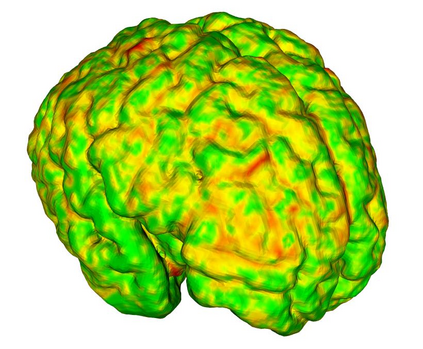

Fetal cortical plate segmentation is essential in quantitative analysis of fetal brain maturation and cortical folding. Manual segmentation of the cortical plate, or manual refinement of automatic segmentations is tedious and time-consuming. Automatic segmentation of the cortical plate, on the other hand, is challenged by the relatively low resolution of the reconstructed fetal brain MRI scans compared to the thin structure of the cortical plate, partial voluming, and the wide range of variations in the morphology of the cortical plate as the brain matures during gestation. To reduce the burden of manual refinement of segmentations, we have developed a new and powerful deep learning segmentation method. Our method exploits new deep attentive modules with mixed kernel convolutions within a fully convolutional neural network architecture that utilizes deep supervision and residual connections. We evaluated our method quantitatively based on several performance measures and expert evaluations. Results show that our method outperforms several state-of-the-art deep models for segmentation, as well as a state-of-the-art multi-atlas segmentation technique. We achieved average Dice similarity coefficient of 0.87, average Hausdorff distance of 0.96 mm, and average symmetric surface difference of 0.28 mm on reconstructed fetal brain MRI scans of fetuses scanned in the gestational age range of 16 to 39 weeks. With a computation time of less than 1 minute per fetal brain, our method can facilitate and accelerate large-scale studies on normal and altered fetal brain cortical maturation and folding.